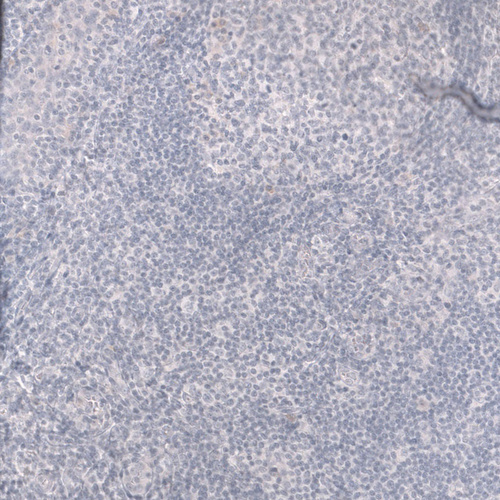

Immunohistochemistry analysis in human heart muscle and skeletal muscle tissues using AMAb91857 antibody. Corresponding TNNT2 RNA-seq data are presented for the same tissues.